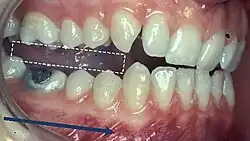

When describing the relationship between maxillary and mandibular incisors, the following categories make up Angle's incisal relationship classification:

- Class I: Mandibular incisors contact the maxillary incisors in the middle third or on the cingulum of the palatal surface

- Class II: Mandibular incisors contact the maxillary incisors on the palatal surface, in the gingival third or posterior to the cingulum. This class may be further subdivided into division I and division II:

- Class III: Mandibular incisors occlude with the maxillary incisors on the palatal surface, in the incisal third specifically or anterior to the cingulum

- In some cases the overjet is reversed (<0mm) and the mandibular incisors lie anterior to the maxillary incisors

When discussing the occlusion of the posterior teeth, the classification refers to the first molars and may be divided into three categories:

- Class I: The mandibular first molar occludes mesially to the maxillary first molar, with the mesiobuccal cusp of maxillary first molar occluding in the buccal groove of mandibular first molar

- Class II: The mesiobuccal cusp of the maxillary first molar occludes anterior to the buccal groove of the mandibular first molar

- Class III: If the mesiobuccal cusp of the maxillary first molar occludes posterior to the buccal groove of the mandibular first molar[8]

5) Contacts in ICP

Begin by assessing the incisor and molar relationship as described above. Similarly examine the overbite and overjet. An overbite of 3-5mm[2] and an overjet of 2-3mms are considered to be within the range of normal.[13]